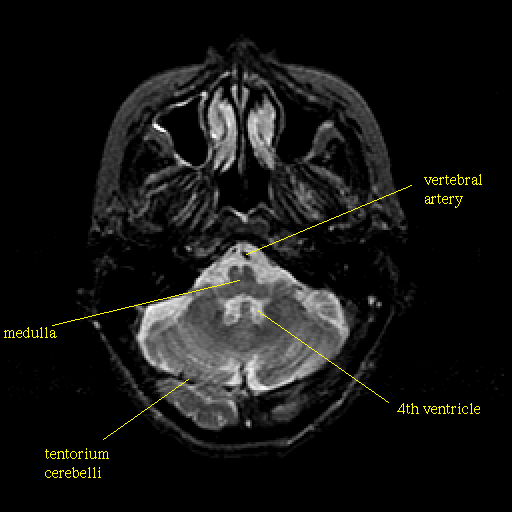

T2-weighted structural MR: Slice 12

Slice 12